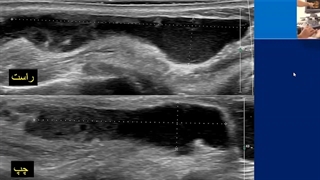

پخش صدا جواب سونوگرافی اشتراکگذاری لیست پخش ۰ نظر ۰ نظر دانلود دانلود ویدیو دانلود کیفیت 720p ۸.۲۶ مگابایت دانلود کیفیت 480p ۵.۷۰ مگابایت دانلود کیفیت 360p ۴.۱۷ مگابایت دانلود کیفیت 240p ۲.۷۱ مگابایت دانلود کیفیت 144p ۱.۷۷ مگابایت گزارش تخلف بیشتر گزینههای بیشتر لیست پخش لایکها گزارش تخلف ۰ لایک دکتر مریم شریفی منتشر شده در تاریخ ۱۴۰۱/۱۲/۰۱ این کانال دنبال شد دنبال کردهاید دنبال کردن این کانال دنبال کردن ادامه نظرات لبخند لبخند لغو ثبت نظری برای نمایش وجود ندارد.